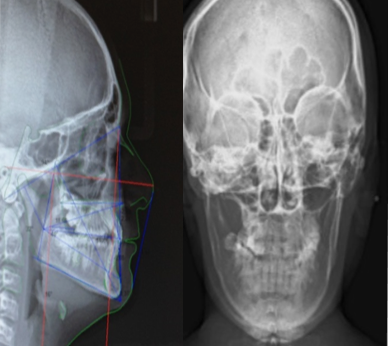

Sistema informatizado en la obtención de 20 tipos de trazados cefalométricos digitales de tejidos blandos y duros, para la realización de diagnóstico , tratamiento ortodóncico y quirúrgico ortodóncico.

Telerradiografías de perfil

Telerradiofrafías de frente

Perfilograma de tejidos

duros y blandos